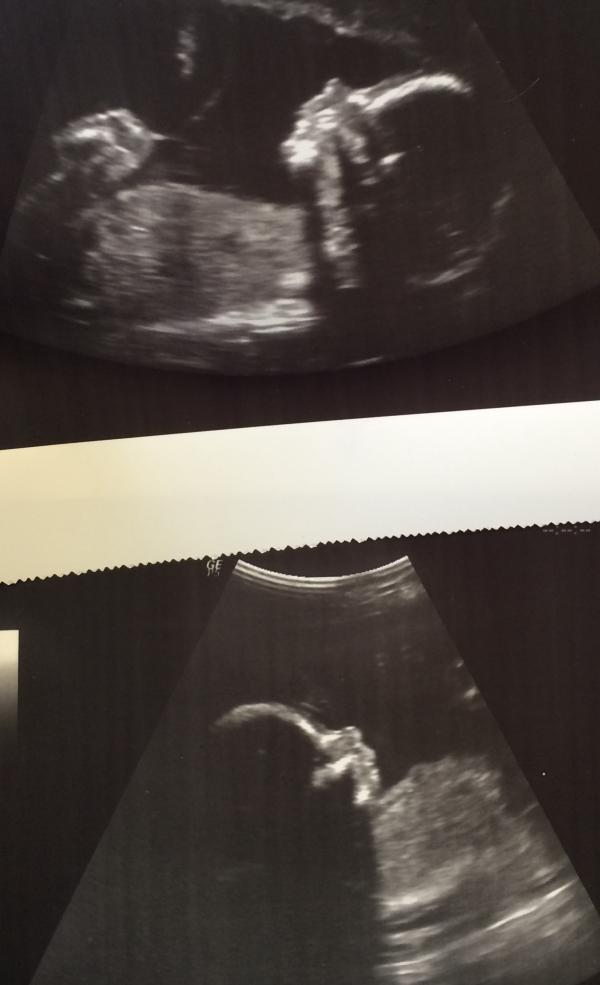

#2скрининг #19недель #денисовичи #двойня